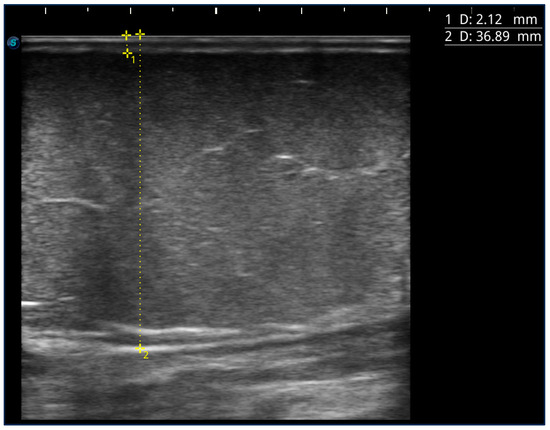

The thickness of the subcutaneous tissue was measured in nine sites of the lower limb. Considering all the patients evaluated, the thickness of the skin increased significantly with the clinical stage at the level of all points, except for the area at the trochanter level. The thickness of the adipose tissue increased progressively with the clinical stage, with a significant difference in all nine points evaluated (p < 0.001 for all points).

Considering the measurement of adipose tissue referring to the lower medial third of the leg in this subpopulation, it was possible to analyze the correlation with other parameters concerning the clinical history and the blood tests. This subpopulation of 102 patients, aged between 13 and 67 years (average 40.4 ± 11.2 years) with a BMI between 20 and 56 (average 27.6 ± 13.1), the following distribution by stage was found: stage 1, 37.3% (38/102); stage 2, 39.2% (40/102); stage 3, 23.5% (24/102).

The thickness of the adipose tissue at this level varied from 7.1 mm to 53 mm (mean 22.1 ± 7.6 mm) and increased progressively with the severity of the stage (p < 0.001). The thickness of the adipose tissue at this level correlated with the thicknesses measured in all other points of the lower limb (p < 0.001 for all points). The thickness was not statistically correlated with age, age of onset, disease duration, and years of treatment with estrogen-progestins. There were no differences in thickness between those who had a family history of lipedema or obesity, those who had used or not used estrogen-progestins, and those who had spontaneous pain or not. The thickness, as expected, correlated positively with all anthropometric parameters, i.e., BMI (p < 0.001), waist circumference and hip circumference (p < 0.001), and WHrT (p < 0.001), while it did not correlate with WHR. The thickness correlated positively with the total pain score (p = 0.003).

There is little research using ultrasound on lipedema, and it is not easy to compare our results. In a previous study, Amato et al. established clinical applicability criteria with simple and reproducible ultrasound cut-off values for the diagnosis of lipedema in the lower limbs. They suggested a cut-off of 11.7 mm for pre-tibial region thickness measurements, with better accuracy, followed by a cut-off of 17.9 mm for the thigh and a cut-off of 8.4 mm for the lateral leg thickness for the diagnosis of lipedema. The optimal cut-off value for the supramalleolar thickness was 7.1 mm, but the accuracy of the diagnosis at this level was lower than at the other points. The supramalleolar thickness showed statistically significant differences between individuals with and without lipedema, but when reanalyzed using stratification by BMI, the supramalleolar thickness was not statistically significant in the normal weight subgroup. Nevertheless, in our population, in no case was the thickness measurement less than 7.1 mm [25].

Marshall et al. suggested the classification of lipedema based on the thickness of the subcutaneous tissue measured at this point: from 12 to 15 mm thickness, it was compatible with lipohyperplasia or mild lipedema; from 15 to 20 mm, it was compatible with moderate lipedema; a thickness greater than 20 mm was compatible with an indisputable diagnosis of lipedema; and one greater than 30 mm with severe lipedema [26]. Although the cut-off used to define a severe clinical condition of lipedema was similar to what was found in stage 3 patients in our population, it is impossible to make a direct comparison due to the different clinical classifications. Some other studies have been performed to identify ultrasound features, such as the thickness and echogenicity of skin and subcutaneous tissue, for the differential diagnosis between lipedema and lymphedema [27].

In our work, ultrasound was used, in support of the evaluation, as a first instrumental approach to exclude the diagnosis of lymphedema by evaluating the dermal thicknesses, the presence and the aspect of inguinal lymph nodes, and the thickness and appearance of the subcutaneous tissue.

In our opinion, the ultrasound measurement of the thickness of the subcutaneous superficial adipose tissue at the level of the lower medial third of the leg could be a simple and quick measurement to perform, which, as was found, correlates with the clinical stage of the disease in type 3 lipedema. The ultrasound study of adipose tissue is a simple and repeatable method that helps to define the disease’s clinical severity and could be used for the monitoring of the evolution of the disease and the response to treatment over time. However, these data must be re-evaluated in more homogeneous and comparable populations.

Most patients also underwent an ultrasound study of the areas affected by lipedema to measure the skin and subcutaneous tissue’s thickness. At the level of the lower limbs, measurements were carried out at 9 different points, 5 of which corresponded to the pain detection points already described above, except for the rear calf area and lower abdomen: the medial upper third of the leg, medial and lateral lower third of the thigh, lateral upper third of the thigh, and medial upper third of the thigh. In addition to the locations in common with pain detection, the measurement was also carried out at the level of the lower medial third of the leg (3–5 cm above the medial malleolus), at the level of the lower lateral third of the leg (3–5 cm above the lateral malleolus), and at the upper lateral third of the leg and upper anterior third of the thigh (approximately 5 cm below the inguinal crease in the anterior region of the thigh) (Figure 4). The measurement was performed using a high-frequency linear probe of 8–14 MHz (SonoScape X3, SonoScape Medical Corp, Shenzhen, China), keeping the probe perpendicular to the skin and without applying pressure to the underlying tissue. For each point, two measurements were carried out: the thickness of the skin measured from the skin surface to the lower edge of the epidermis and dermis complex, and the thickness of the suprafascial superficial adipose tissue, measured from the surface of the skin to the muscle fascia (Figure 5).